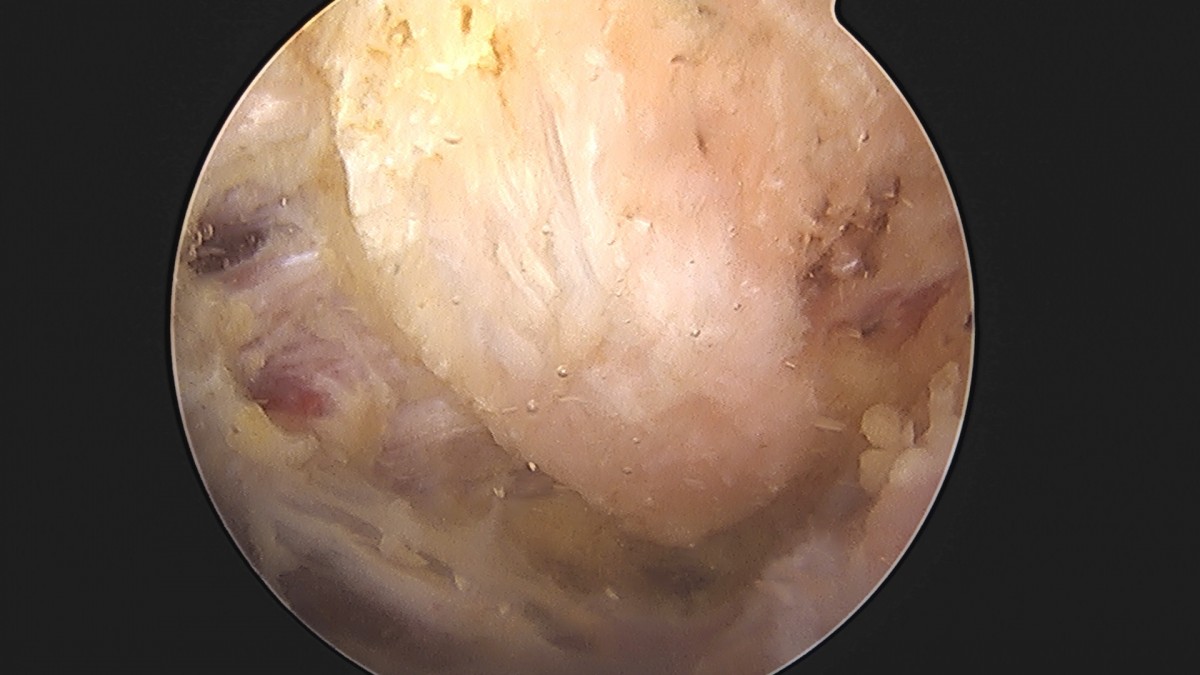

이재상원장님 어깨 견봉하 감압술 및 석회 제거술 이형O 환자

작성자 최고관리자 댓글 0건 조회 746회 작성일 25-09-16 15:40